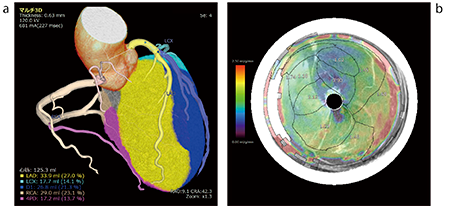

CT装置のX線管球の高出力化および管球の回転速度高速化による時間分解能の向上,体軸方向の検出器幅の増加といったハードウエアの性能向上,逐次近似画像再構成法に代表される画像ノイズの低減化や濃度分解能向上などのソフトウエアの技術向上により,CT装置で心臓領域における冠動脈,心筋,心室などの形態情報に加え,薬剤負荷を実施後にダイナミック撮影することで時相ごとの血流情報を得ることができるようになった。これらの画像をVINCENTの“心筋パフュージョン(CT)” “心臓フュージョン”といった循環器領域の解析アプリケーションを利用することにより,虚血領域の観察および前述したMMARとの融合画像の作成を容易に行える(図2)。

図2 心臓フュージョンの解析画像

a,bは異なる症例である。

a:各支配領域結果を3D表示に重ね合わせた画像例

b:支配領域結果と心筋パフュージョンで得られた機能画像を融合した画像例